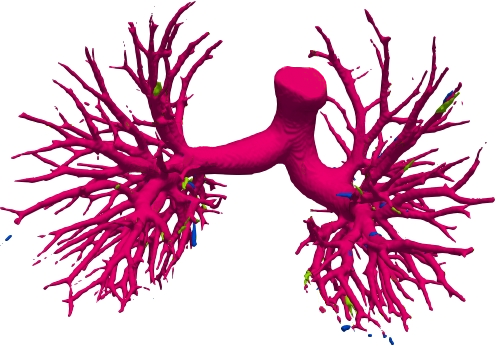

We qualitatively analyze our method on four challenging lung organ datasets. In Fig. 5, SFCN [19] suffers from severe false positives and some false negatives, especially for the big green areas of airway leakages. WNet [22] is mainly influenced by false negatives on the main trachea. For the Fibrosis dataset at the third row, it also encounters the false negative problem in the terminal bronchioles moderately. FANN [10] bears the slight discontinuity issue of false negative in the terminal bronchioles of BAS dataset, and the severe discontinuity and airway leakage problems on the more challenging Fibrosis benchmark. Instead, due to the above two novel modules, our method can solve the defects of false negative, discontinuity, and leakages faced by past advanced methods. Besides, the results on PARSE22 artery dataset in supplementary Fig. 6 also proves this.